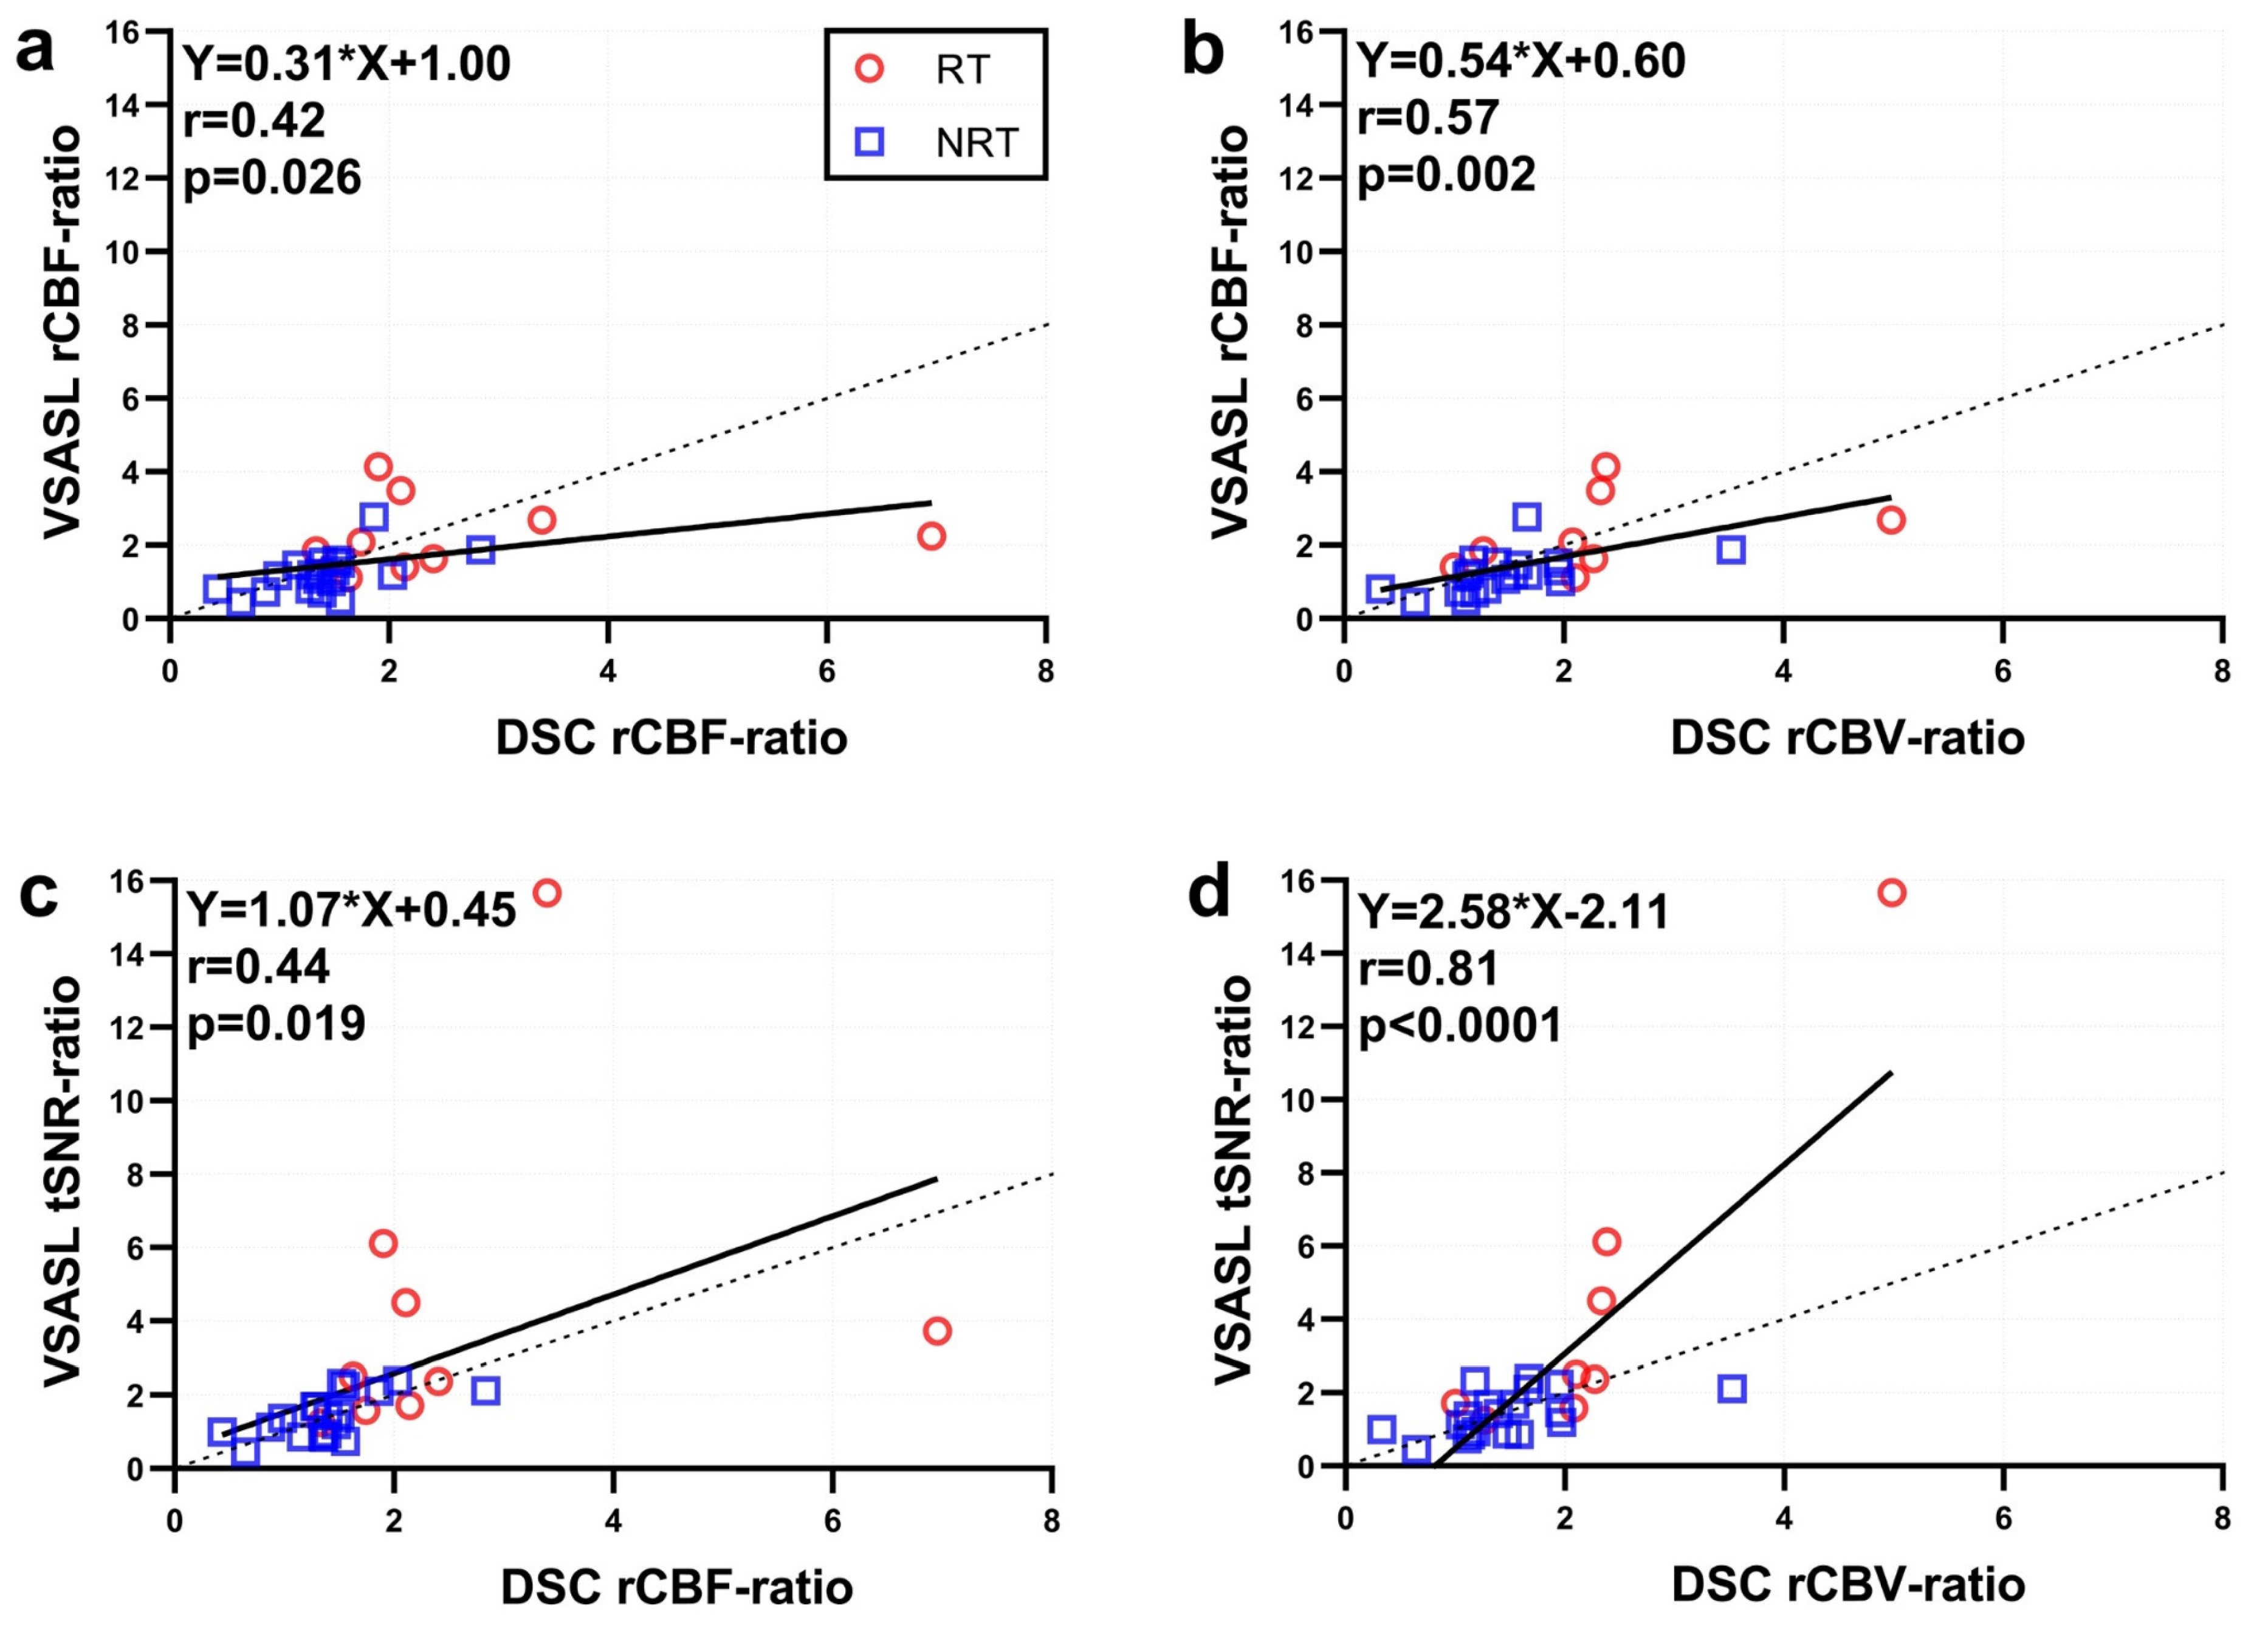

3. Results